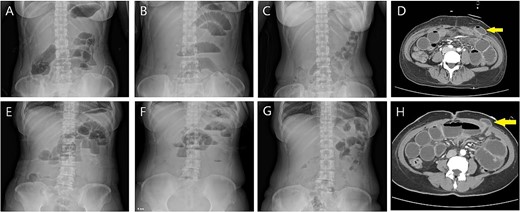

On postoperative day (POD) #1, she complained of abdominal distension with mild nausea and vomiting. An abdomen X-ray showed air-fluid levels (Fig. 2A). Follow-up X-ray revealed aggravated ileus on POD#4 (Fig. 2B). An abdominal computed tomography (CT) scan demonstrated small bowel obstruction due to herniation at the left 8-mm port site (Fig. 2D), with the drain in situ. Emergency exploration showed that herniation occurred along with the left port site drain tract; however, there was no sign of bowel injury. Surgical repair was done, and the patient recovered well (Fig. 2C).

(A) Case 1: abdomen X-ray on POD #1; prominent small bowel gas with air-fluid level. (B) POD #4: aggravated ileus. (C) POD #7 after robotic myomectomy (POD #3 after exploration): recovered to a nonspecific normal gas pattern. (D) Small bowel herniation (arrow) is noticed at the left mid-axillary trocar site on a CT scan. (E) Case 2: abdomen X-ray on POD #3; mild ileus with air-fluid level (F) POD#6 on the morning of surgery: persistent ileus with L-tube in situ. (G) POD #9 after robotic myomectomy (POD #3 after exploration): nonspecific bowel gas shadow. (H) Small bowel herniation (arrow) is noticed at the left mid-axillary trocar site on a CT scan.

A 51-year-old woman with multiple growing myomas visited our clinic with abdominal discomfort and frequent urination. Her BMI was 24.80 kg/m2. Imaging evaluation with magnetic resonance imaging and ultrasonography revealed multiple myomas, with the largest diameter of 12.3 cm. She underwent 3RPM on 28 February 2022, in the same manner as the patient described above. She had postoperative nausea, which aggravated on POD#3. Her abdomen X-ray demonstrated mild ileus, which aggravated over time (Fig. 2E, F). Her abdominal CT revealed an incisional hernia on the left trocar site accompanied by small bowel obstruction (Fig. 2H). On POD#6, she underwent incisional hernia repair, and bowel perfusion remained unimpaired. She recovered well and her X-rays showed nonspecific findings (Fig. 2G).